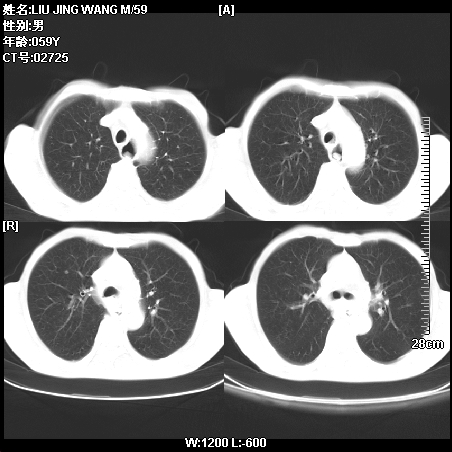

标题: CT14028:M59Y,这两例两下肺病变相同吗?

肿瘤科住院病人,都有食管癌史,都有放化疗治疗,两下肺病变是转移灶?还是其他原因造成?请老师指点

病例一 现呼吸困难,经抢救多次,咳嗽咳痰,发现食管癌2个多月

符合放射性肺炎,第一例不除外坠积效应